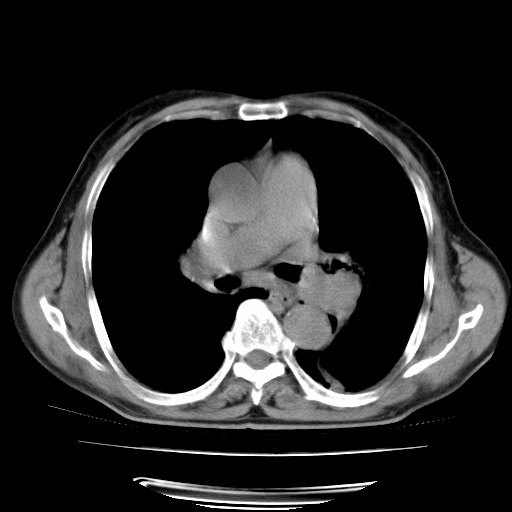

男,71岁,咳嗽,气喘10年,再发并咯血.胸片见气胸

考虑  左肺中心型肺癌伴阻塞性肺炎,肺不张,纵膈淋巴结肿大。慢支炎,肺气肿,左侧气胸肺压缩5%

左侧中央型肺癌伴纵膈淋巴结转移。

左肺中心型肺癌伴阻塞性肺炎,肺不张,纵膈淋巴结肿大

1)考虑左肺中心型肺癌伴阻塞性肺炎、左肺下叶肺不张、左侧肺气肿,纵膈淋巴结转移。2)左侧气胸(肺组织压缩约5%)。

1)考虑左肺中心型肺癌伴阻塞性肺炎、左肺下叶肺不张、左侧肺气肿,纵膈淋巴结转移。2)左侧气胸。